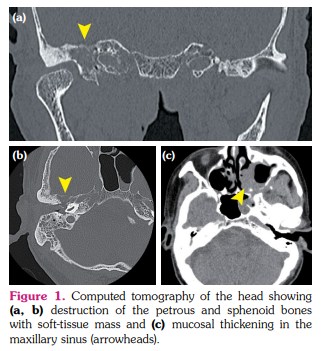

An 80-year-old man with a history of diffuse large B-cell lymphoma (DLBCL) presented to the otolaryngology department due to hearing loss and fullness in the right ear. He was diagnosed with primary testicular DLBCL five years earlier, but complete remission was sustained after treatment. Computed tomography identified a soft-tissue mass in the right middle ear and mastoid cells, along with destruction of the petrous and sphenoid bones with soft-tissue mass and mucosal thickening in the maxillary sinus (Figure 1a-c). A weakly positive result was obtained for serum proteinase 3-anti-neutrophil cytoplasmic antibody (PR3-ANCA), at 5.2 IU/mL. The patient was referred to our department on suspicion of granulomatosis with polyangiitis (GPA) and otitis media with ANCA-associated vasculitis (OMAAV). He showed no other symptoms suggestive of systemic vasculitis, and serum soluble interleukin-2 receptor was slightly elevated to 643 U/mL (normal: <610 U/mL). The T2-weighted magnetic resonance imaging (MRI) showed signal hyperintensity in the right mastoid, suggesting mastoid effusion (Figure 2a). However, contrast-enhanced MRI revealed enhancement around the mastoid cells and cranial base and nodules in the maxillary sinus (Figure 2b, c). Diffuse large B-cell lymphoma was diagnosed from biopsied mucosa in the maxillary sinus, with no findings of granuloma or vasculitis.

Positive results for ANCA are sometimes seen in patients with infection, inflammatory bowel disease or malignancy, including malignant lymphoma (ML), and not just in cases of vasculitis.[1,2] The precise mechanisms remain unclear, but neutrophil infiltration in response to tissue damage by ML or lymphoid cell-derived factors have been hypothesized to produce ANCA.[3] Some reports have described cases of ML mimicking GPA with craniocervical or otolaryngologic manifestations, such as sinusitis, otitis, nasal obstruction and discharge, masses in the nasal cavity, hypertrophic pachymeningitis and infarction of the pons.[4,5] Although GPA was suspected due to craniocervical or otolaryngologic manifestations in these patients, no kidney involvement was found.[4] Malignant lymphoma should, thus, be considered in patients without typical presentations such as glomerulonephritis, but differentiating between the two entities is practically difficult. A previous study comparing ANCA-positive patients with a clinical diagnosis of AAV from those without a clinical diagnosis of AAV demonstrated that a higher ANCA titer (≥4 times the upper limit of normal) and the number of affected organ systems (≥2 organ systems) may help to discriminate AAV from other diseases with positive results for ANCA.[2] A study investigating the characteristics of primary skull base lymphoma showed the usefulness of MRI to distinguish ML from other pathologies mimicking ML.[6] The combination of imaging findings, restricted diffusion on diffusion-weighted imaging, surrounding hyperostosis, bony erosion and/or marrow signal replacement, and heterogeneous contrast enhancement may raise suspicion for skull base lymphoma.[6] Our patient exhibited a lower ANCA titer, and a soft-tissue mass in the right middle ear and mastoid cells, along with destruction of the petrous and sphenoid bones and contrast enhancement of the mass on MRI without other organ involvements, suggesting ML. As a result, ML should be excluded using the degree of elevation of the ANCA titer, affected organ systems and MRI findings, when GPA limited to the ears, nose and throat is suspected.